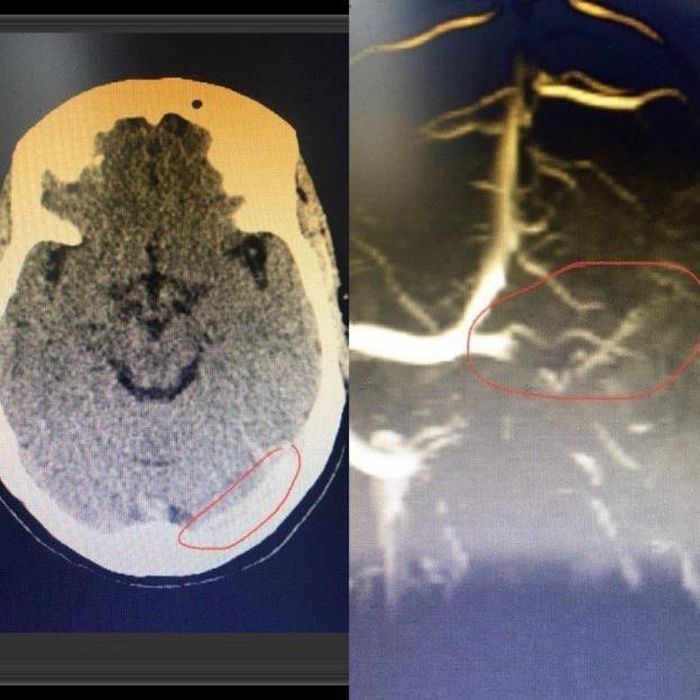

Bệnh nhân được điều trị tại Khoa Tâm thần kinh. Các bác sĩ chụp cắt lớp vi tính sọ não nhận thấy có hình ảnh dải tăng tỷ trọng nhu mô vùng chẩm bên trái. Sau khi thảo luận, các bác sĩ quyết định chụp cộng hưởng từ não – mạch não, kết quả bệnh nhân bị tắc hoàn toàn xoang tĩnh mạch ngang bên trái.

Hình ảnh cắt lớp vi tính và MRI sọ não của bệnh nhân. (Ảnh BVCC)